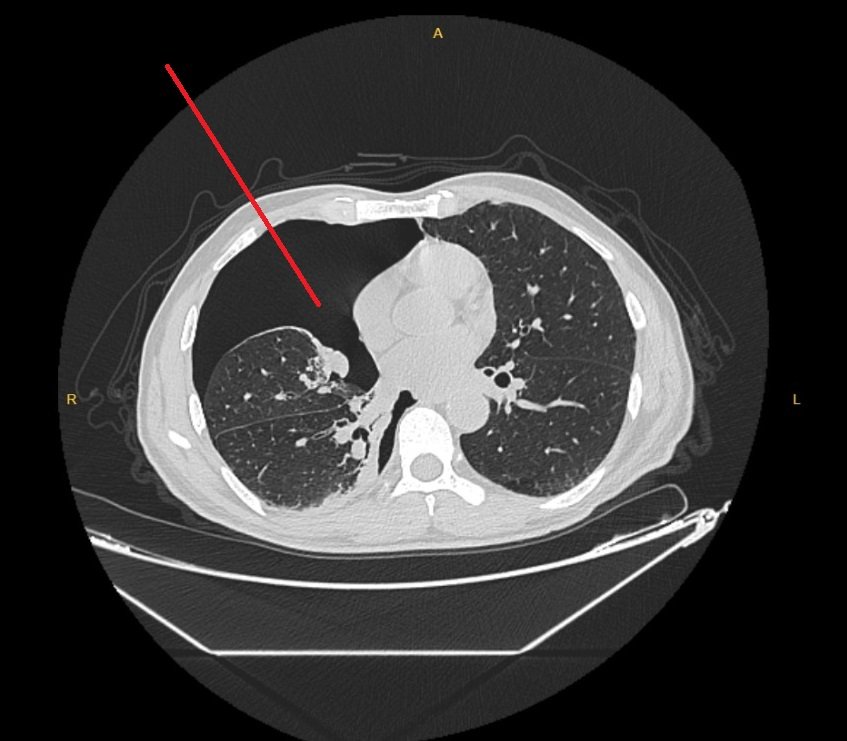

BT (Bilgisayarlı Tomografi)

- Gri tonlar yerine siyah alanlar hava dolu boşlukları belirtir